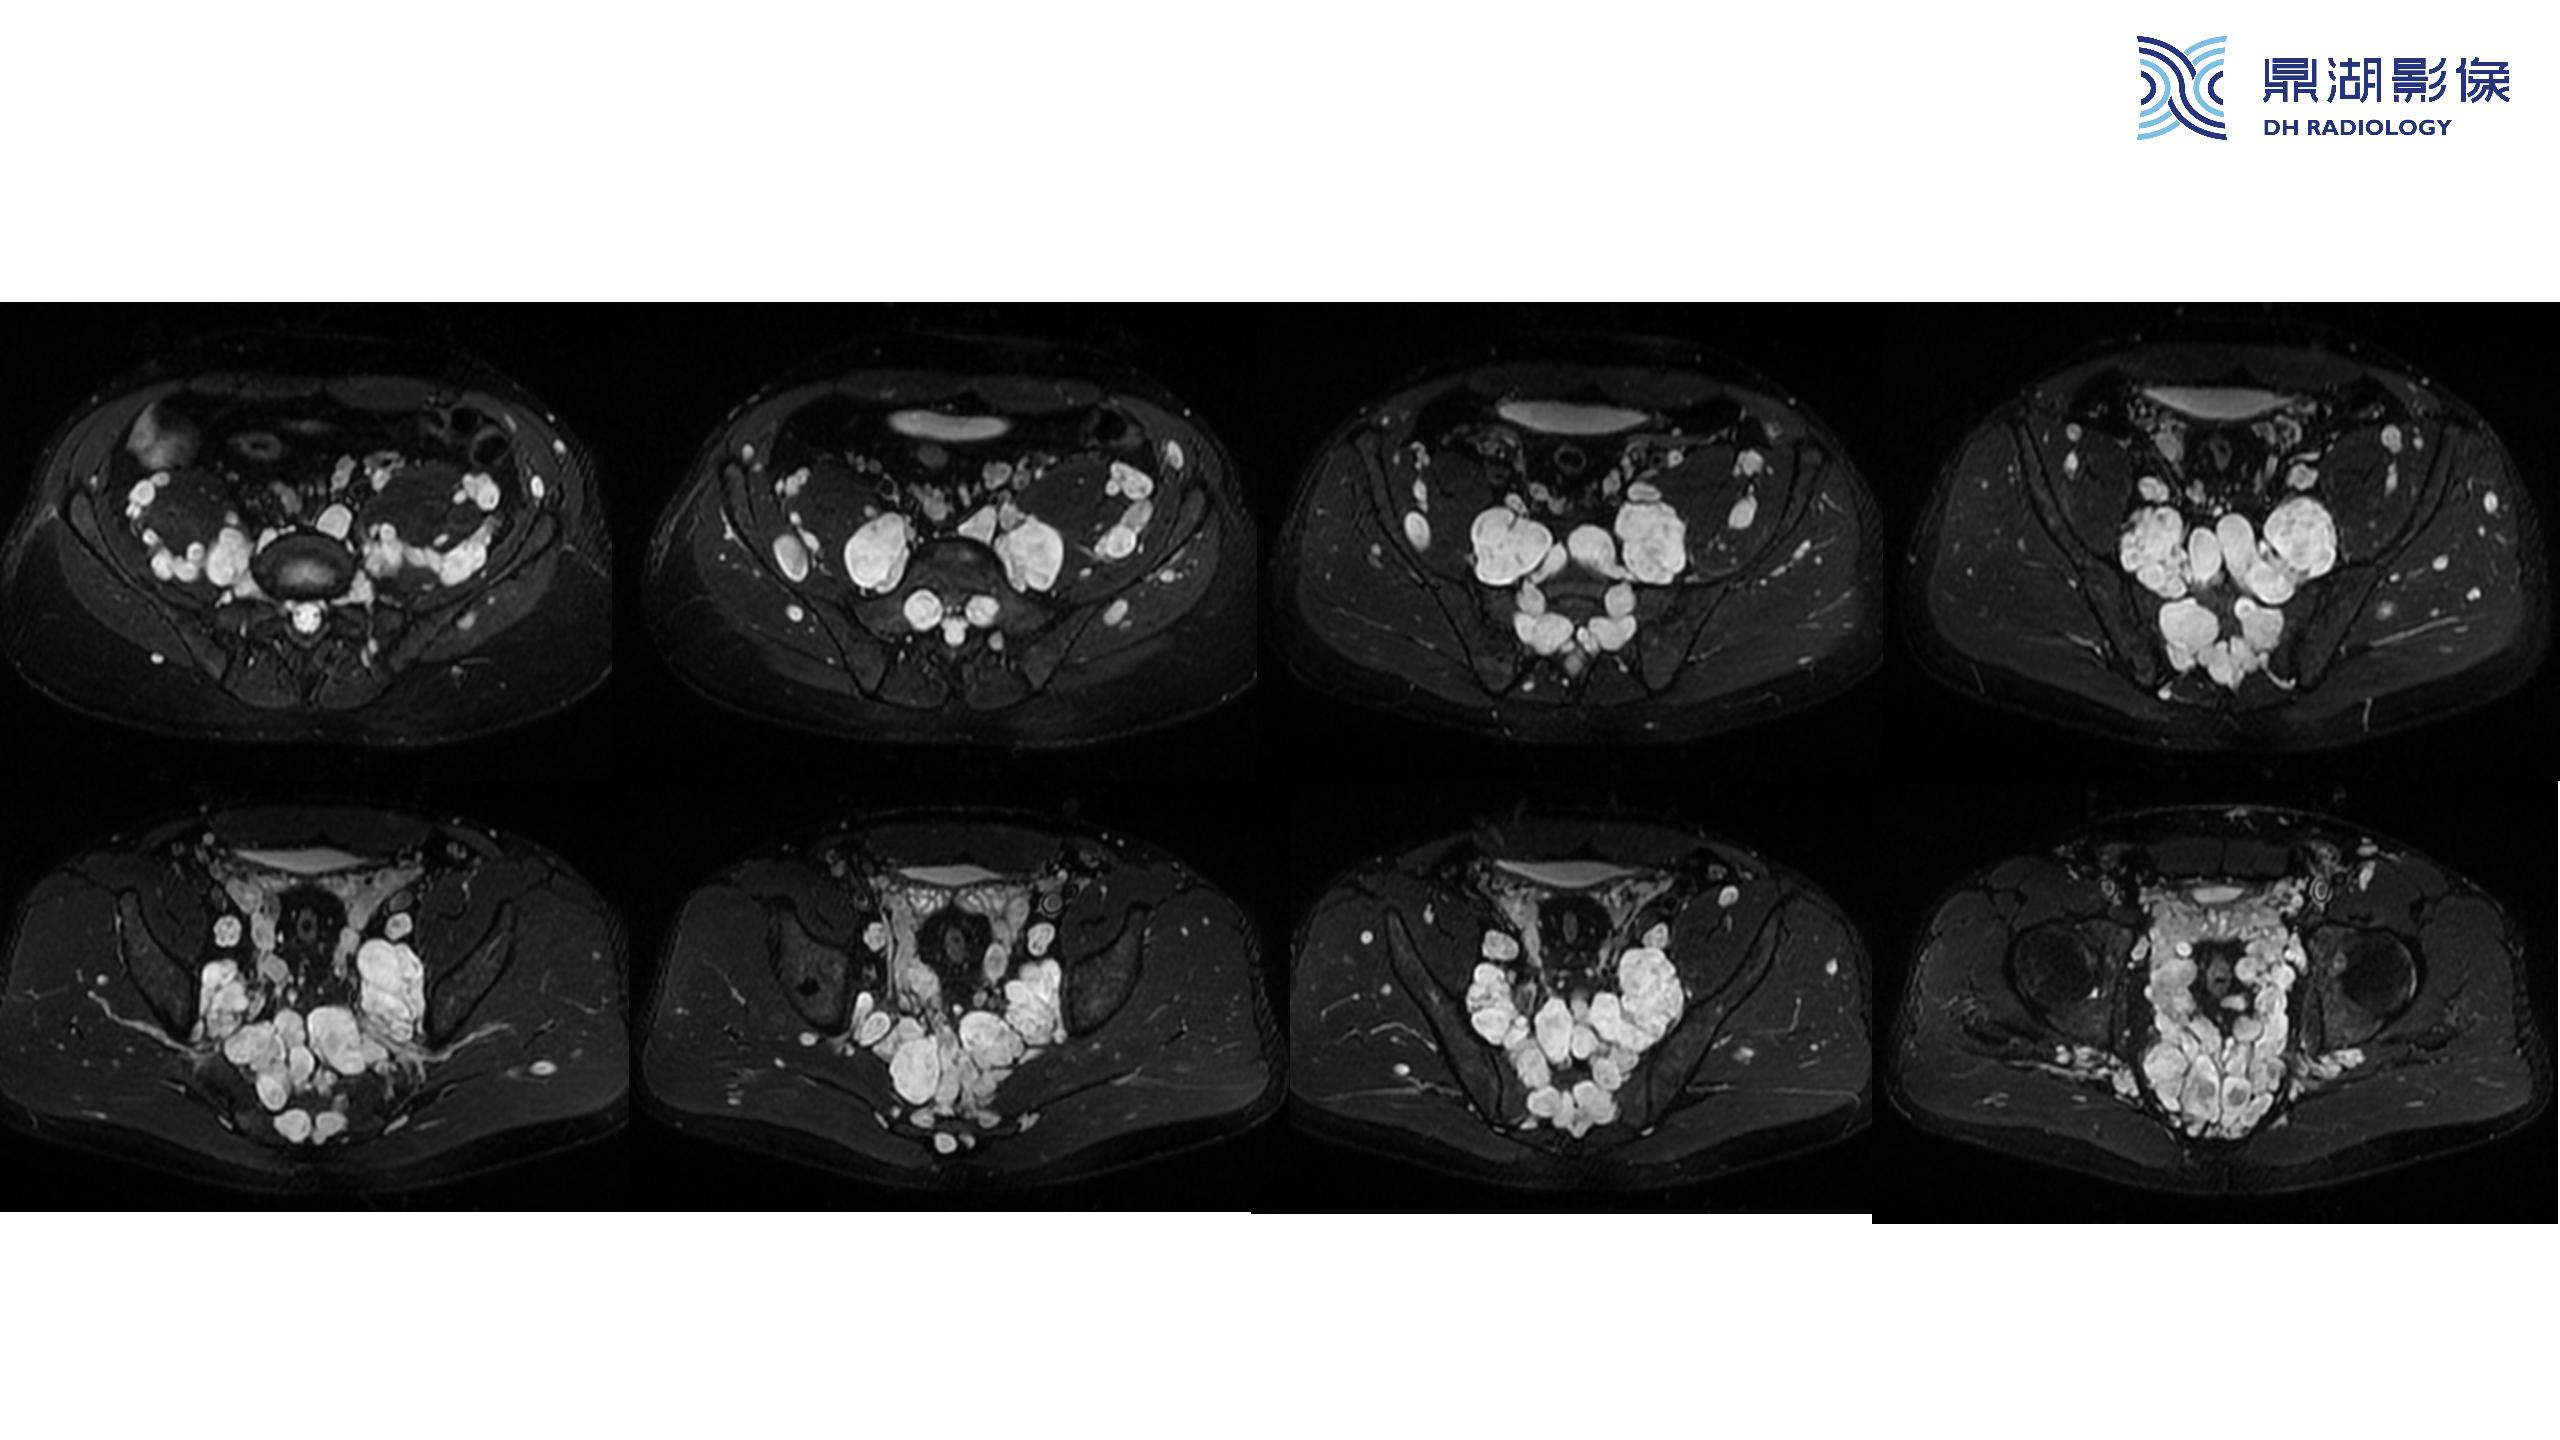

神经纤维瘤病(NF1)